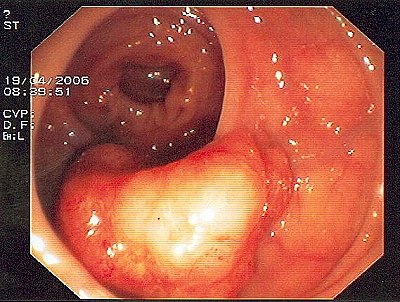

Großer Polyp des Dickdarmes